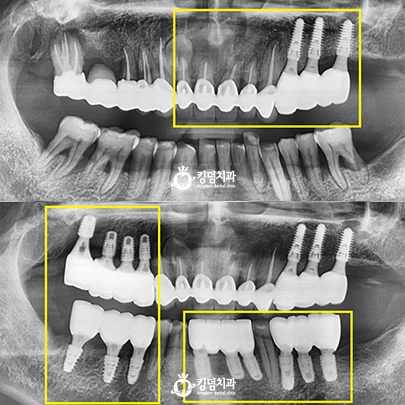

• 킹덤치과 전후사진

• 잇몸뼈 녹음, 2차 충치

• Before After

• 압도적인 실력과 신뢰의 차이